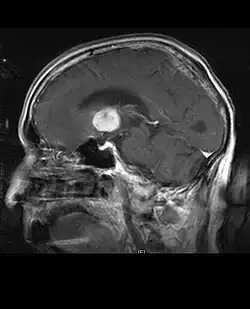

Durch Computertomographie (CT) und Kernspinresonanztomographie (MRT) kann eine Neoplasie im Gehirn effektiv nachgewiesen werden. Zur Identifizierung von Läsionen ist die MRT empfindlicher als die CT, weist aber für Patienten mit Herzschrittmachern, inkompatiblen Prothesen, Metallklammern und anderem Kontraindikationen auf. Die CT bleibt die Methode der Wahl, um Verkalkungen innerhalb der Läsionen oder Knochenerosionen der Schädeldecke oder -basis zu erkennen. Die Verwendung von Kontrastmitteln, die im Fall der CT jodiert und im Fall der MRT paramagnetisch (Gadolinium) sind, ermöglicht die Erfassung von Informationen über die Vaskularisation und Integrität der Blut-Hirn-Schranke, eine bessere Definition der Tumorgeschwulst im Vergleich zum umgebenden Ödem und die Erstellung von Hypothesen über den Grad der Malignität. Die radiologische Untersuchung ermöglicht auch eine Bewertung der mechanischen Auswirkungen und die daraus resultierenden Veränderungen der Gehirnstrukturen, die sich durch den Tumor ergeben, wie zum Beispiel Hydrocephalus und Hernien, deren Auswirkungen tödlich sein können. Schließlich kann mit dieser Diagnostik in Vorbereitung einer Operation der Ort der Läsion oder die Infiltration des Tumors in lebenswichtige Bereiche des Gehirns bestimmt werden. Zu diesem Zweck ist die MRT effizienter als die CT, da sie dreidimensionale Bilder liefern kann.[4]

Diagnostische radiologische Bildgebungsinstrumente heben die Veränderung des neoplastischen Gewebes im Vergleich zum normalen Gehirnparenchym hervor (durch Änderungen der elektronisch dargestellten Dichte des Gewebes bei der CT und der Signalintensität bei der MRT). Wie die meisten pathologischen Gewebe sind auch Tumoren durch eine erhöhte Ansammlung intrazellulären Wassers erkennbar. Im Computertomogramm erscheinen sie hypodens, das heißt von geringerer Dichte als das Gehirnparenchym, im Kernspinresonanztomogramm bei Spin-Gitter-Relaxation hypointens und bei Spin-Spin-Relaxation sowie Protonengewichtung (PD) hyperintens.[5][6]

Auf einer radiologischen Aufnahme sollte der gesunde Gehirnbereich keine besondere Lumineszenz aufweisen. Daher ist es selbstverständlich, dass auf größere Kontrastsignalbereiche geachtet wird.

Im Tumorgewebe ist im Allgemeinen der größere Anteil der Kontrastverstärkung auf die besondere Blut-Tumor-Schranke zurückzuführen, die den Durchgang von Iod (CT) und Gadolinium (MRT) in den intratumoralen extravaskulären Interstitialraum ermöglicht. Dadurch steigt das Signal (Dichte oder Intensität) des Tumors. Es sollte jedoch darauf geachtet werden, dass die Kontrastverstärkung die Neoplasie von Periwundödemen nicht mit Sicherheit abgrenzt. Tatsächlich zeigt der anatomisch-pathologische Befund bei malignen infiltrierenden Gliomen Tumorgewebe, wie zum Beispiel beim Glioblastom und anaplastischem Astrozytom, auch jenseits des vasogenen Ödems, das durch die Zerstörung der Blut-Hirn-Schranke durch den Tumor verursacht wird. Letzterer klinischer Zustand ist durch diagnostische Bildgebung schlecht nachweisbar.[5][6]

Die Computertomographie des Gehirns zeigt typischerweise eine Gewebsmasse, die entweder durch Kontrast verstärkt werden kann. Bei der CT erscheinen niedriggradige Gliome normalerweise isodens zum normalen Parenchym und zeigen daher möglicherweise keine Kontrastverstärkung. In ähnlicher Weise sind Läsionen in der Fossa cranii posterior, der hinteren Schädelgrube, im CT schwer zu identifizieren. Folglich sind die Ergebnisse einer solchen Tomographie allein nicht immer für diagnostische Zwecke ausreichend.[4] In zweifelhaften Fällen ist die Verwendung der empfindlicheren Kernspintomographie unerlässlich.

Auf -Kernspintomogrammen erscheint ein intrakranieller Tumor als massive Läsion, die nach Verwendung des Kontrastmittels lumineszierender werden kann. Eine Signalanomalie gibt es jedoch immer in -Kernspintomogrammen, die auf das Vorhandensein einer Neoplasie oder eines vasogenen Ödems hinweist. Normalerweise ist eine stärkere Lumineszenz (Kontrastverstärkung) ein Hinweis auf einen Tumor höheren Malignitätsgrades. Ein Kontrastring ist charakteristisch für ein Glioblastom, wobei der Lumineszenzanteil dem lebenswichtigen Teil des bösartigen Tumors und der dunklere -hypointense Bereich der Gewebenekrose entspricht.[4]